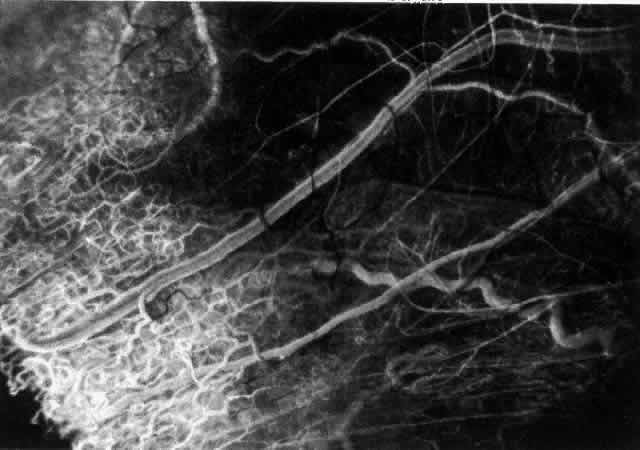

The characteristic features of necrotizing scleritis on fluorescein angiography

are hypoperfusion and, eventually, nonperfusion of the vascular

networks (Figs. 40 through 43).26 The initial changes are on the venous side of the capillary network; the

transit time of the dye increases even if the eye is red and congested. If

the disease process persists or has been present for a long time, thrombosis

and permanent vaso-occlusive changes occur. These vessels (or

the occluded capillary network) are bypassed by the opening of

anastomotic channels. New vessels in a granuloma give rise to deep intrascleral

leakage of dye (see Fig. 43). Conjunctival and episcleral involvement by the destructive change is

late but is always preceded by vaso-occlusive changes that can sometimes

Fig. 42. Late arterial phase of fluorescein angiogram in a patient with necrotizing

scleritis. All the vessels except the main trunk and the vessels around

the limbal perforating vessels are occluded and remain unperfused

throughout the angiogram. Fig. 42. Late arterial phase of fluorescein angiogram in a patient with necrotizing

scleritis. All the vessels except the main trunk and the vessels around

the limbal perforating vessels are occluded and remain unperfused

throughout the angiogram.

|

Fig. 43. Late venous phase of angiogram of a patient with necrotizing scleritis

showing late deep leakage from vessels on the surface of the sclera and

leakage of the capillary network at the limbus and the vessels draining

it, together with poor or absent perfusion of the remaining vessels. Fig. 43. Late venous phase of angiogram of a patient with necrotizing scleritis

showing late deep leakage from vessels on the surface of the sclera and

leakage of the capillary network at the limbus and the vessels draining

it, together with poor or absent perfusion of the remaining vessels.

|